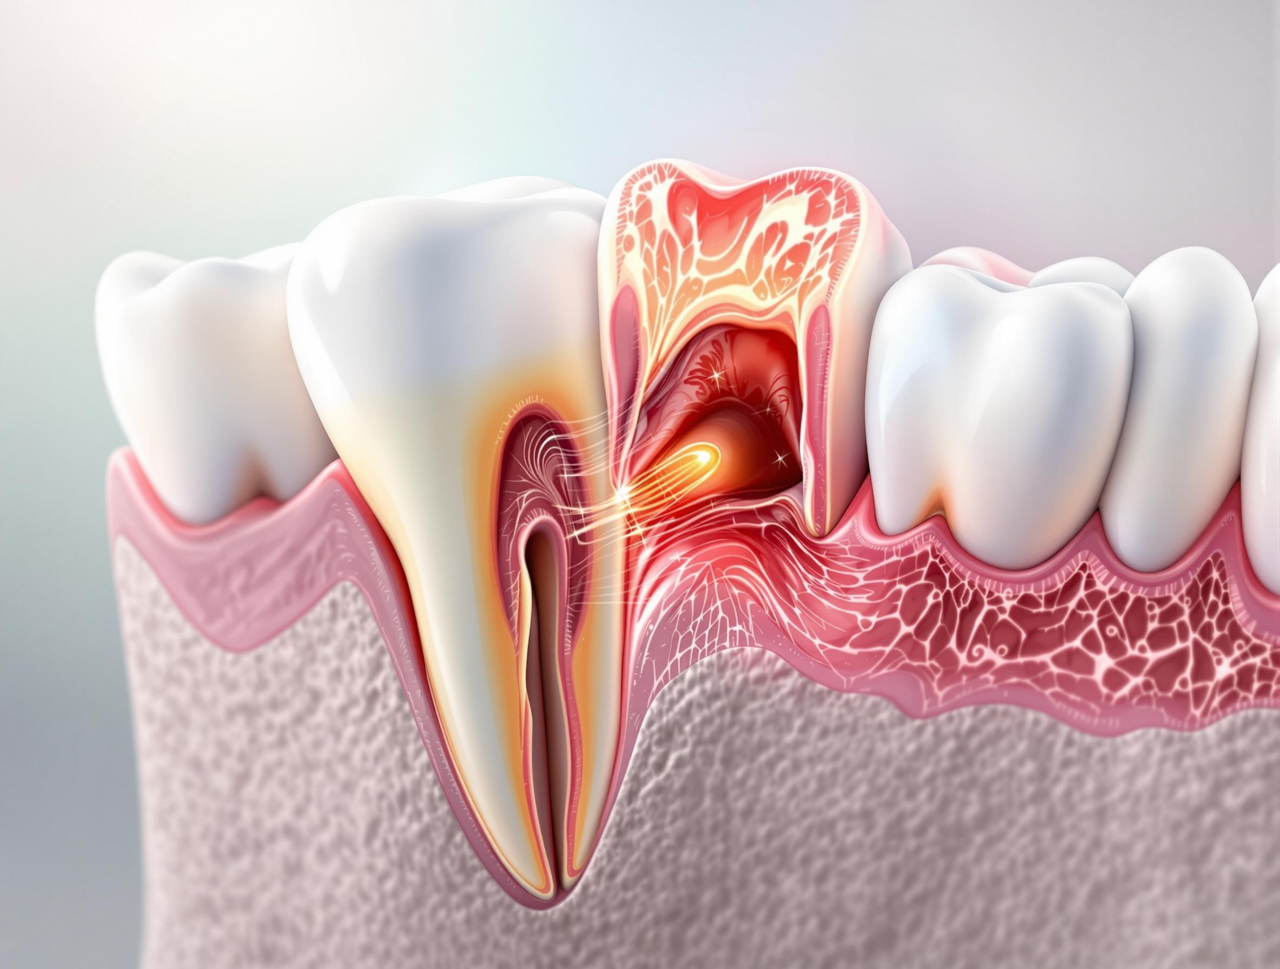

사랑니 주변 잇몸에 염증이 발생하며 잇몸과 볼이 붓게 됩니다.

염증이 심한 경우 낭종, 종양, 골수염 등의 문제를 일으킬 수 있습니다.

사랑니 옆 어금니에 안 좋은 영향을 끼치게 됩니다.

염증으로 인해 사랑니 주위의 뼈가 흡수되어 사랑니 옆 어금니의 치조골도 함께 흡수됩니다.